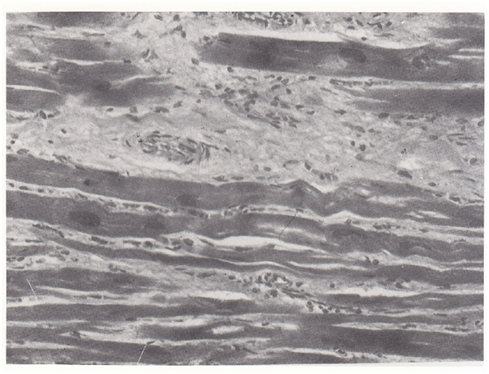

2 pts (4.3%) Table 2 showed sudden H as a symptom of impending rupture (respectively from 118/86 mmHg to 180/95 mmHg and 145/90 mmHg to 190/98 mmHg) and chest pain resistant to opiates. They deceased within 1 hour from increased H. The other 44 pts with PCR were hypertensive in 27 cases (61%) at the admission, while 17 (39%) displayed no H. Pts with rupture (Figures 1-4), and (Table 3) had a statistically significant number of multiple coronary alterations, cardiac hypertrophy (mean heart weight 627+/-188 grams and left ventricle wall thickness 25+/-3 mm vs 400+/-75 grams for heart weight and 14+/-2mm for left ventricle wall thickness in pts with no rupture), irregular areas of confluent fibrosis and coronary narrowing up to 90% with a high incidence of occlusive thrombi.

Figure 3 Microscopic changes in PCR. It can be seen confluent areas of fibrosis with a hemorrhagic occlusion of intramural coronary artery and myocardial fiber fragmentation.